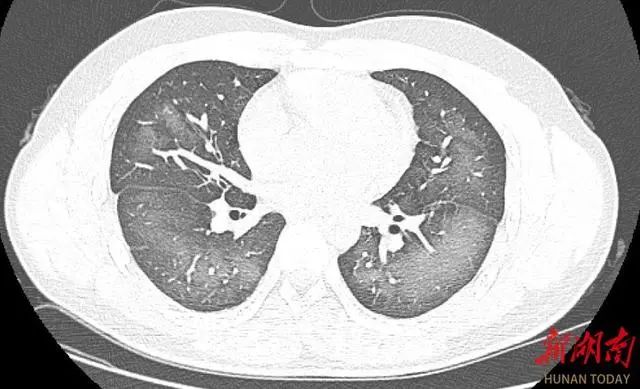

症狀一直持續到第二天仍未好轉,他急忙來到醫院就診。經檢查,肺部CT片顯示該小伙雙肺赫然呈現大範圍白色樣病變,報告提示「白肺」。

「白肺」一般是指重症肺炎在X線或CT檢查下的表現,患者肺部呈現一大片的白色狀態,往往會出現呼吸困難、呼吸衰竭,嚴重者還會出現其他臟器功能障礙。